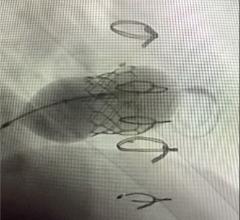

This channel includes news and new device innovations about heart valve technologies, including the aortic valve, mitral valve, pulmonic valve, and tricuspid valve. This includes information on transcatheter valve technologies like transcatheter aortic valve replacement (TAVR, or implantation TAVI), transcatheter mitral valve repair or replacement (TMVR), transcatheter and surgical valve repairs, and surgical replacement valves. Newer devices are now being used for transcatheter tricuspid valve repair replacement (TTVR).